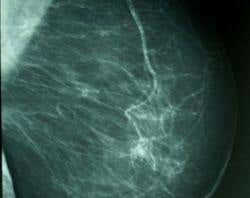

Smart particles of polymer gel that can sieve rare proteins from the blood could allow cancer to be diagnosed at an earlier stage.

Researchers looking for ways to make earlier diagnoses of cancer are concentrating on finding new “biomarkers” – molecules which indicate the presence of tumours before any symptoms show. Among the top candidates are small proteins that tumours shed into the blood. The trouble is that these are present in only minute quantities and so get masked by larger, more common blood proteins, such as albumin.